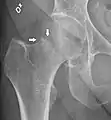

Fracture (black arrow, pertrochanteric) versus a skin fold (white arrow).

X-rays of the affected hip usually make the diagnosis obvious; AP (anteroposterior) and lateral views should be obtained.